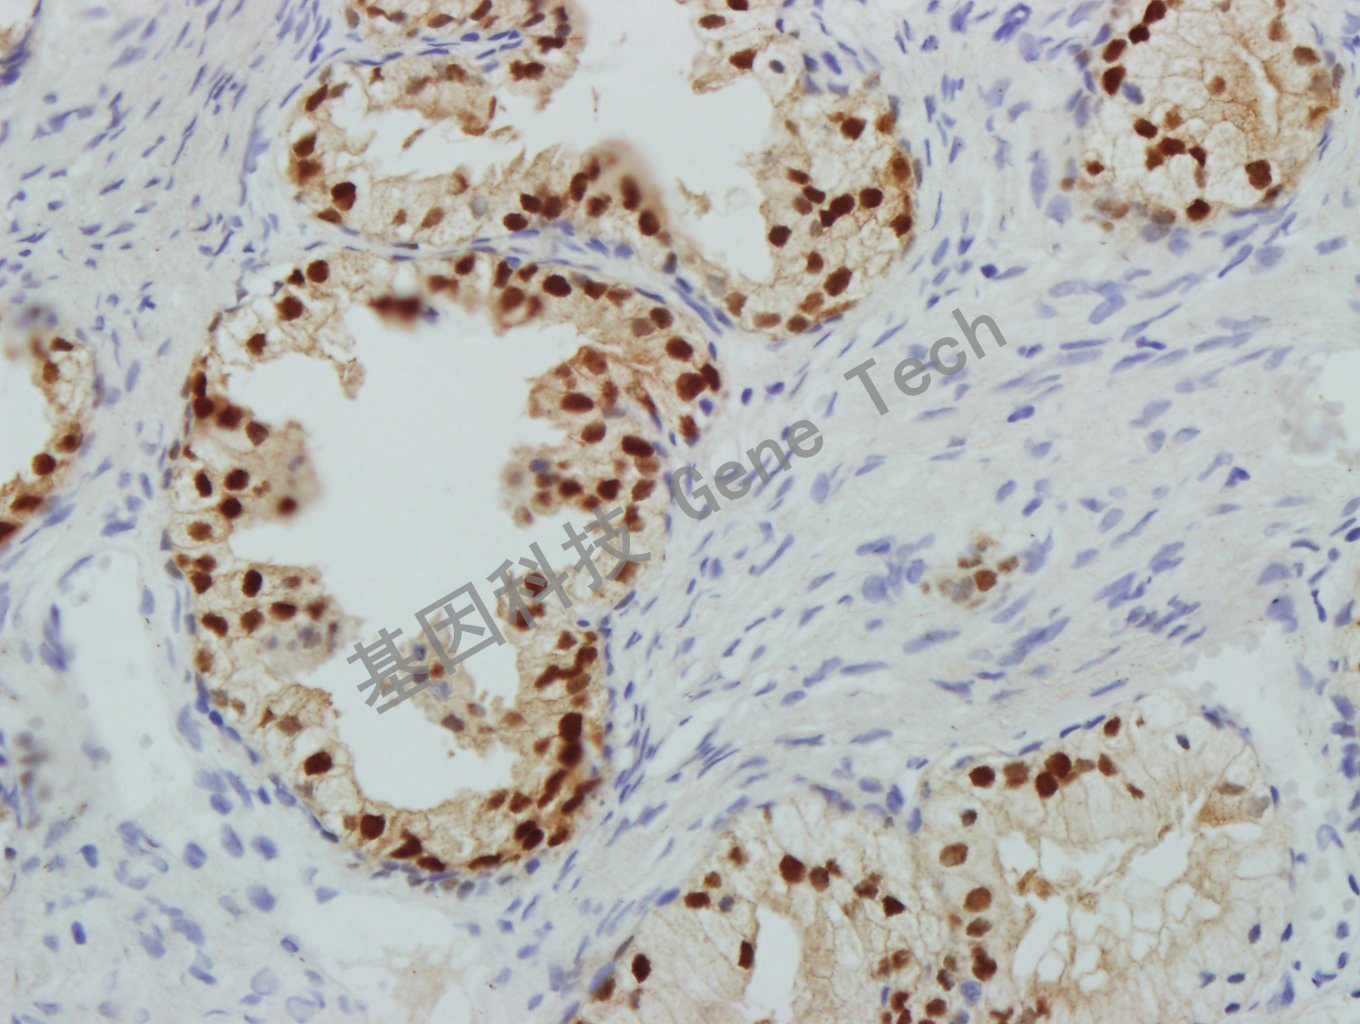

| 預(yù)處理:高pH熱修復(fù) | 陽性部位:細胞核 | 陽性對照:前列腺/腎 |

| 前列腺石蠟切片,用 NKX3.1(GT2260)染色,細胞核陽性,DAB 顯色。 | ||